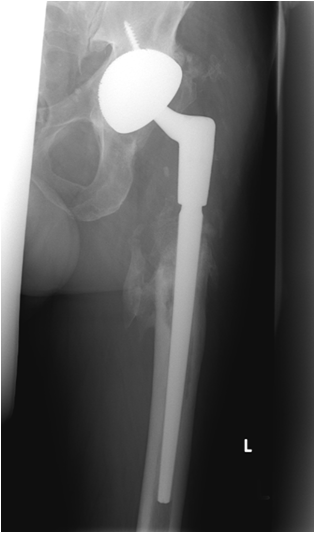

- 6/2010: Cementless revision THR (Acetabular component: Metallsockel 2000, Orthodynamics, Luebeck, Germany; Femoral component: Restoration Modular Stryker, Mahwah, NJ, USA). Microbiology: Five tissue samples and PCR/culture of the spacer sonication fluid without detection of microorganisms

- 7/2011: Clinical and radiological follow-up one year after reimplantation: no clinical or laboratory signs of a relapse of the periprosthetic infection. The X-rays (Figure 4 [Fig. 4]) show moderate ossifications of the soft tissue around the femoral diaphysis without clinical relevance. No signs of implant-loosening or migration.

Figure 4: Cementless total hip revision implant: radiological follow-up 1 year after implantation